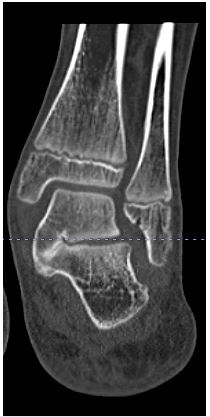

Subtalar arthroereisis is a well-established, extra-articular, minimally invasive surgical option for symptomatic pediatric flexible flatfoot. The most favorable outcomes have been reported in patients aged 9 to 12 years [7–9,18–22]. The procedure corrects excessive hindfoot eversion by stabilizing the subtalar joint in a more aligned position. Various techniques and implants for subtalar arthroereisis have been described. Implants are typically inserted into or adjacent to the sinus tarsi to prevent excessive hindfoot eversion [7–9,18–22]. In the present series, the preferred method involved insertion of a 6.5-mm cancellous bone screw (AO large-fragment set) near the anterolateral edge of the posterior facet of the subtalar joint, beneath the lateral process of the talus (Figure 3). This “calcaneo-stop” screw functions as a mechanical block, limiting hindfoot eversion and maintaining subtalar alignment. At the conclusion of surgery, a bulky soft dressing was applied. Weight bearing as tolerated and range-of-motion exercises were initiated on the first postoperative day.

Figure 3: Screw insertion under lateral process of talus.